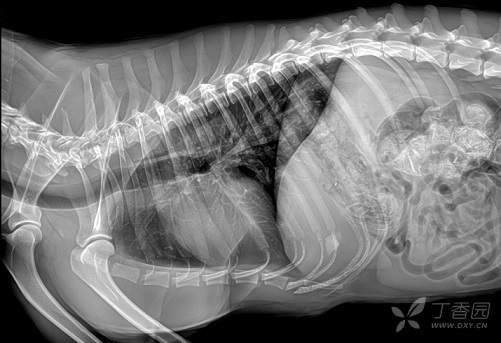

以方博士宠物DR为例,实现了从平板探测器,高频高压发生器,整机控制系统,图像算法软件等全产业链自主研发生产。平板探测器使用430*430mm主流非晶硅材质,图像高清细腻,低噪音;高压发生器采用软开关谐振集输,可达400Khz超高逆变频率,拥有很强的稳定性,保证图像品质输出;宠物医生专用的图像算法软件,基于大数据分析自动调节曝光功能,方便宠医操作;整机控制更加智能。这样不仅做出了拥有特点和优势的产品,也帮助美诺瓦医疗获得了无数良好的口碑,其产品也成为了众多宠物医院的首选。